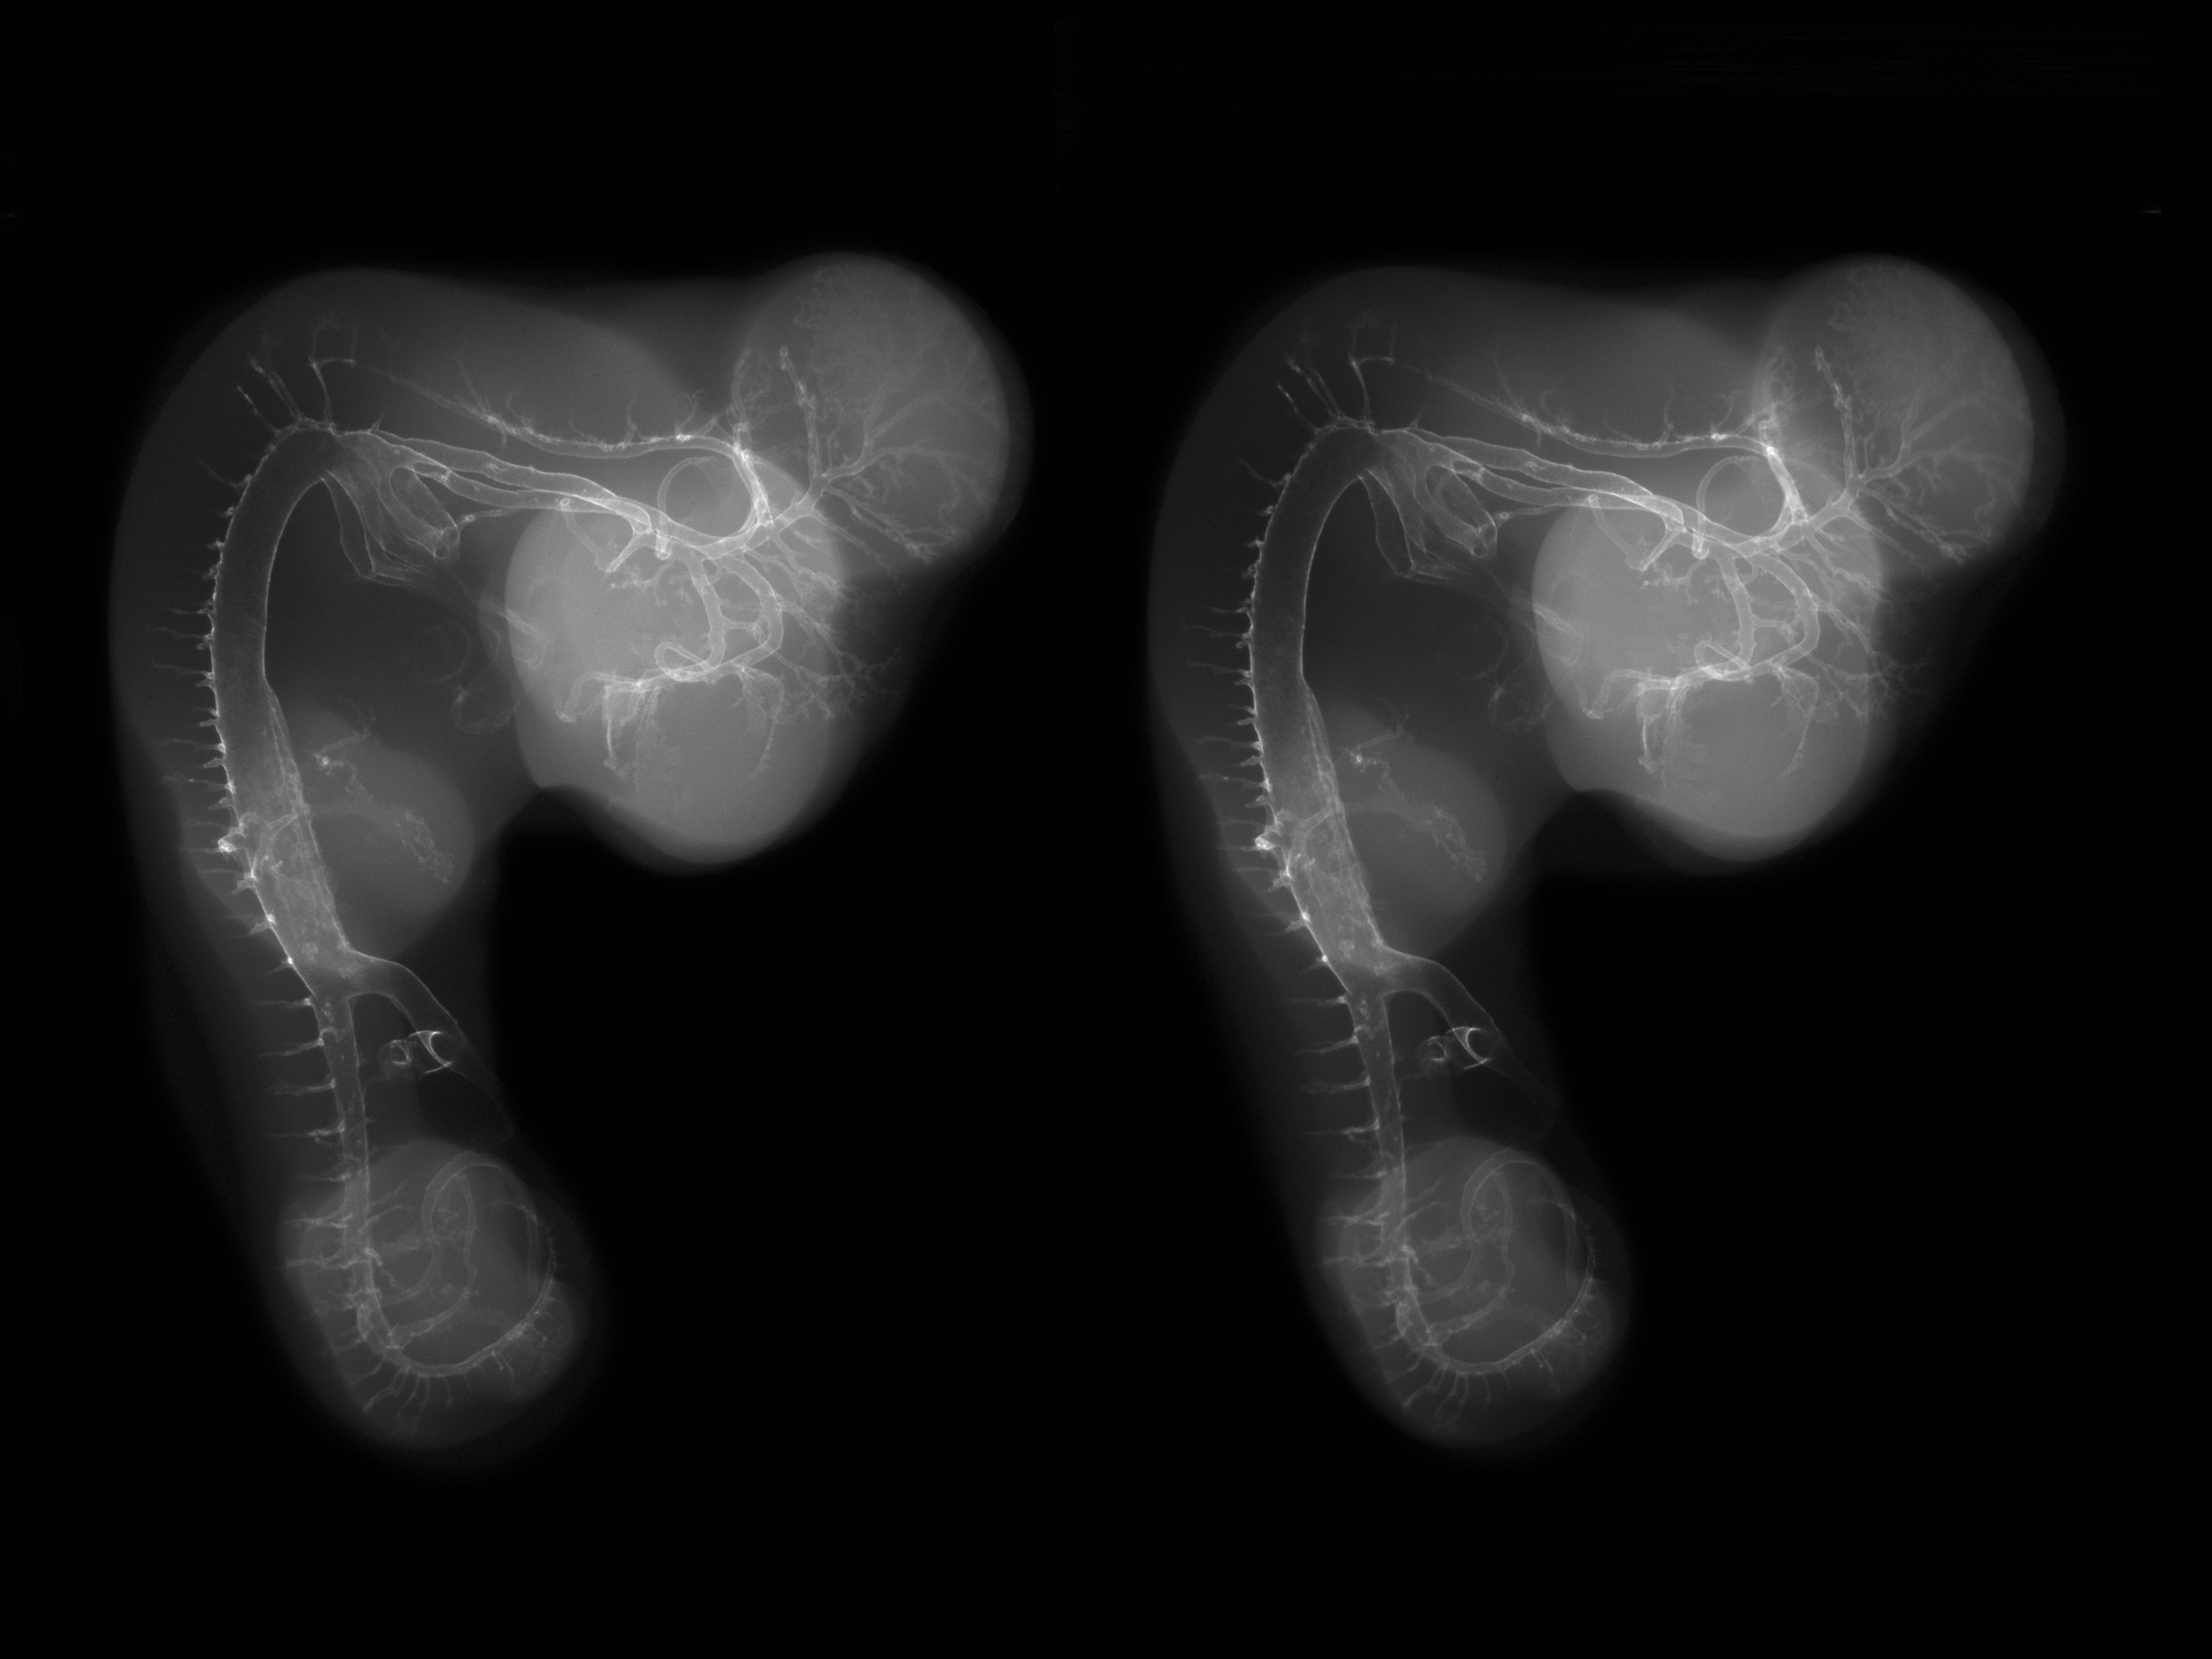

Chick Embryo Microangiography

Hamburger-Hamilton (HH) Stage 25 (approx. 4.5 - 5 days)

Stereo X-Ray Micrographs